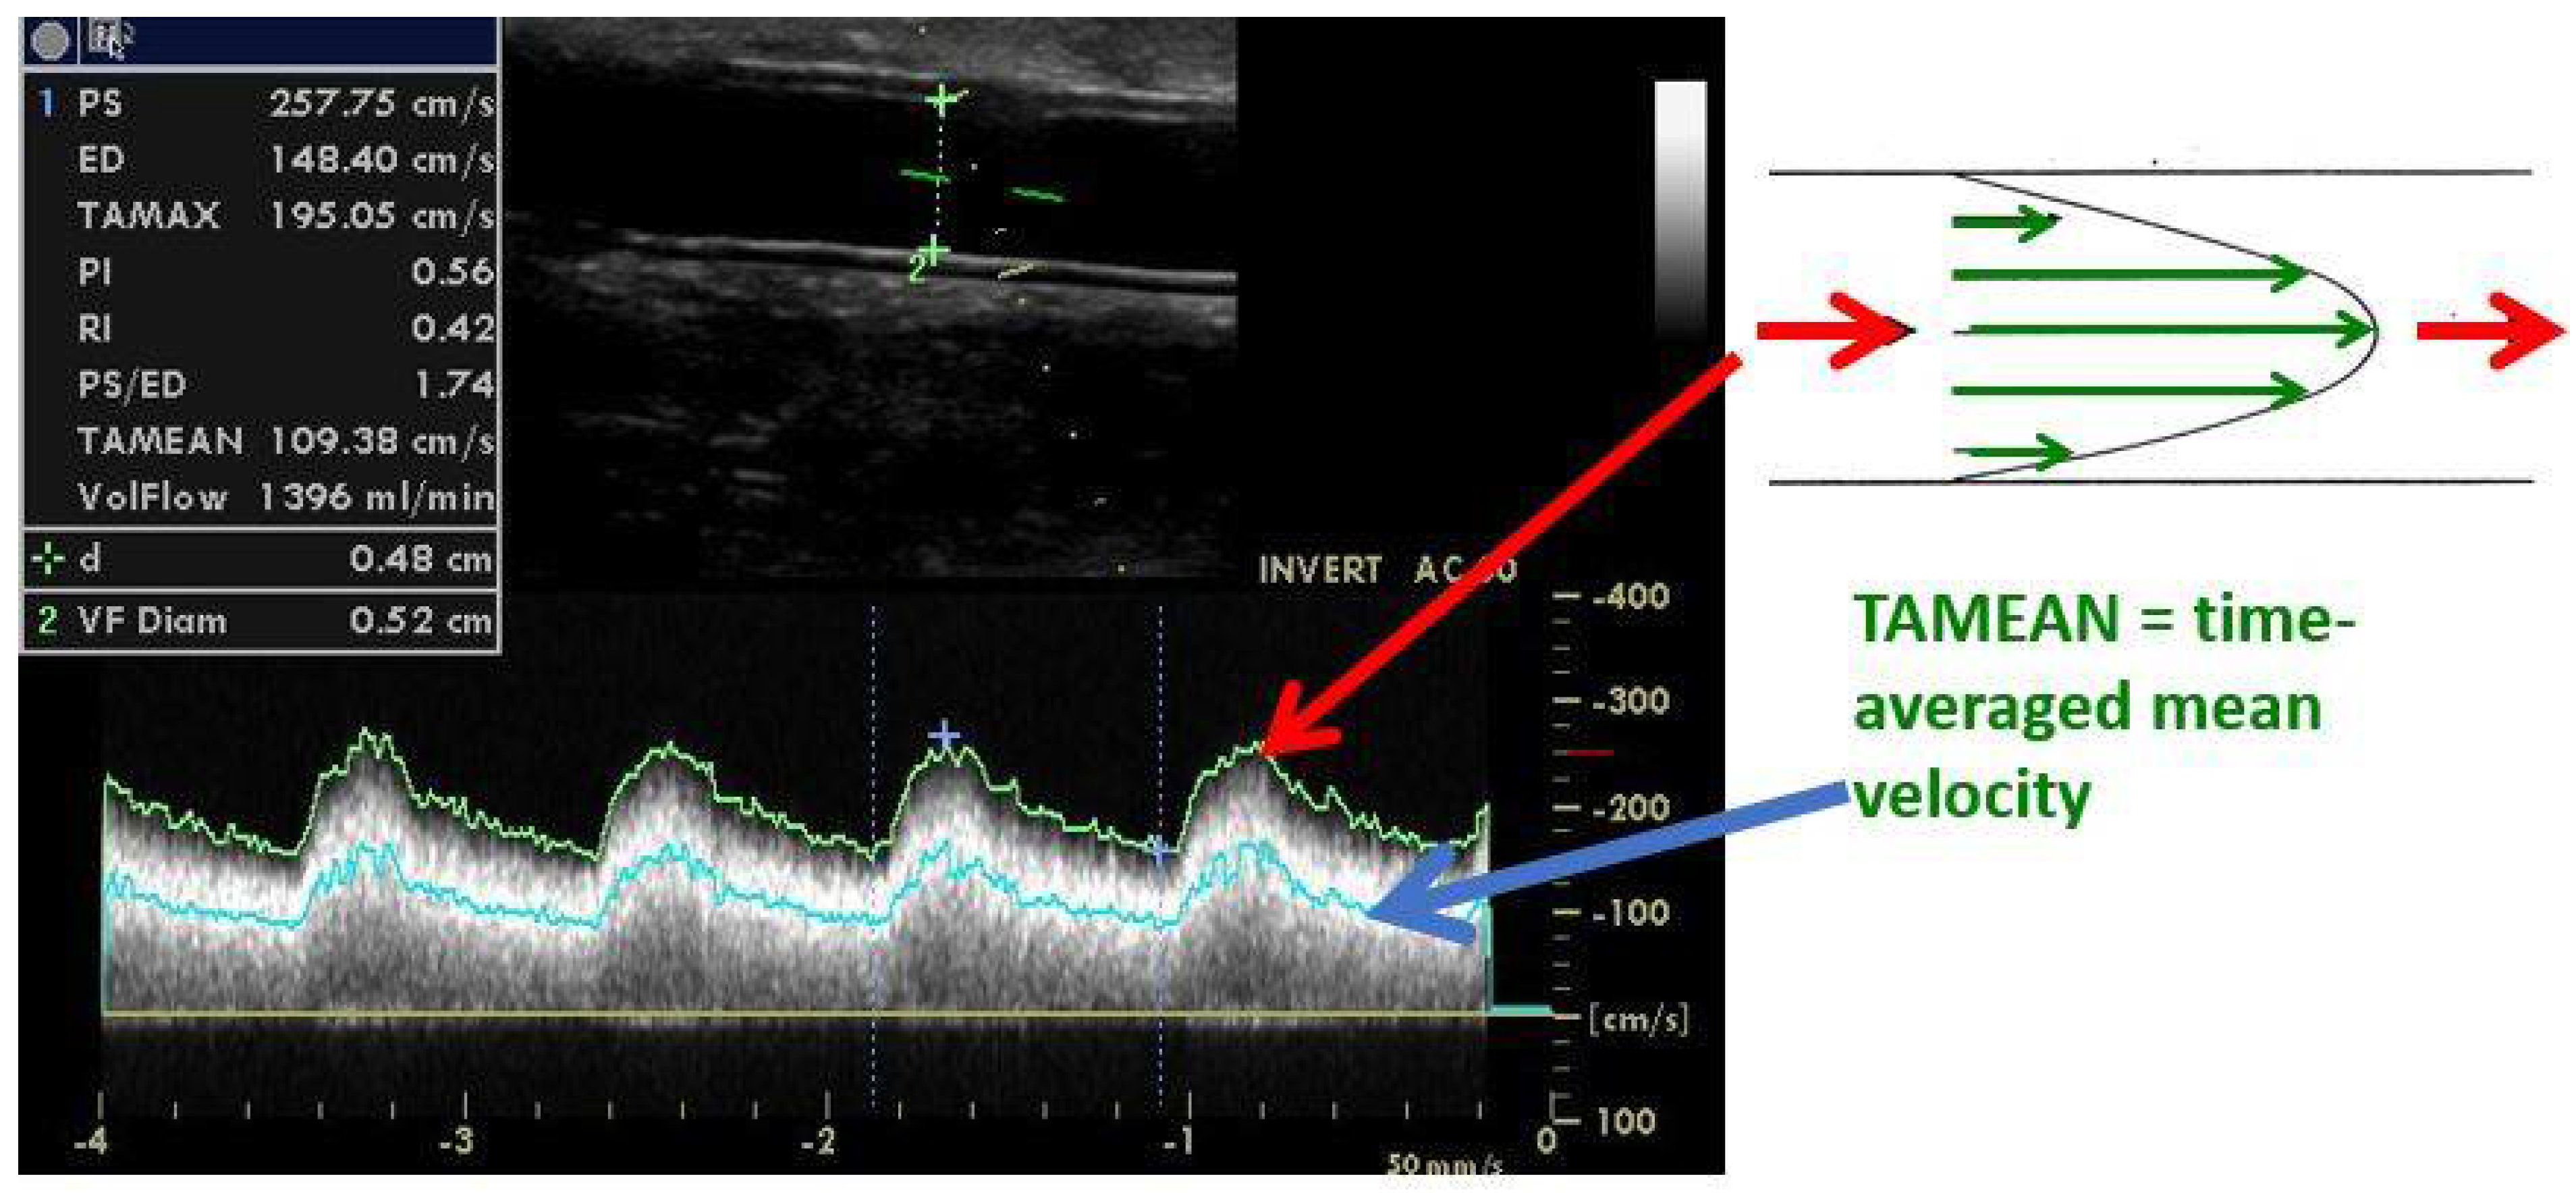

5. Significant Stenosis Definition by Ultrasonography

| Peak systolic velocity increase > 2–3x | |